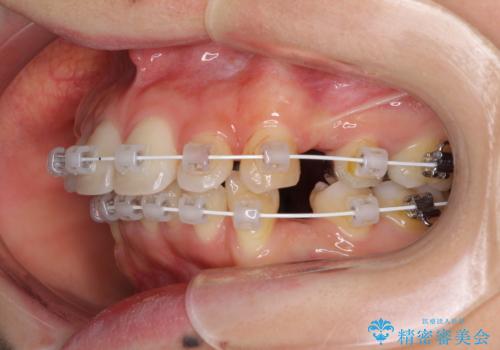

- 審美装置

- 上下の出っ歯を気にして来院された患者様です。

口元を積極的に引っ込めるために、上下左右の第一小臼歯を4本抜歯することとしました。

元々ディープバイトのため、スペースを閉じている期間に上下前歯が接触してしまい、治療期間が想定よりも伸びてしまいました。